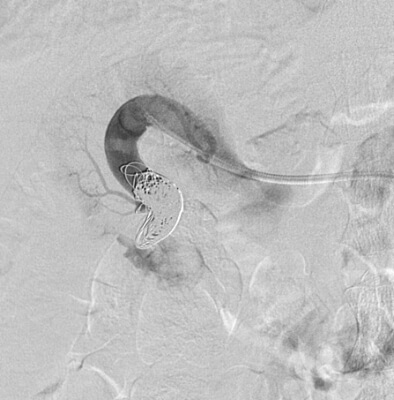

64 year old male who presents with right testicular pain, mild right flank pain, and signs of early CHF.

Comment: This patient presented with scrotal pain, right flank pain, and early CHF. Upon review of the imaging, it became clear that all three of these symptoms were related. The renal angiogram demonstrated prompt opacification of the right renal vein and IVC. This appeared to be secondary to an AV fistula that resulted in increased venous pressure, which contributed to the development of a varicocele (through a branch of the right renal vein draining into the right testicular vein before passing into the IVC). In addition, the outflow from the fistula likely increased right heart pressure, leading to his cardiac symptoms.